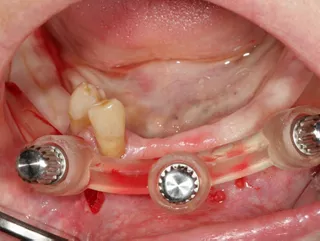

8. Implants are in situ; the procedure was minimally invasive.

9.  Positioning of the Tissue Level temporary abutments platform N plural reference number TC100-N-P to accommodate the prefabricated temporary restoration.